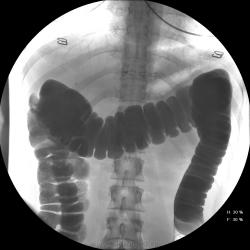

Девушка, 27 лет, жалуется на периодические боли в правой подвздошной области, области паха справа. Во время этого идет нарушение стула - то слабит, то несколько дней не может ходить в туалет, вздутие кишечника. Жалобы несколько лет . Обследованна кем только можно. Хирург посоветовал ирригоскопию. Работа достаточно нервная. До первого случая данных проблем , за неделю, проходила сан лечение в пансионате ( для поднятия общего иммунитета - так говорит), был курс клизм с травами - сама думает, что это не связанно.

Цепочка тенюшек - это наша "гордость)" следы от контраста после гистеросальпингоскопии. чтоб вымыть ,надо разбирать стол , а это только с представителем сименса. вот так.) а правые отделы толстой кишки на расширены? я кроме лополнительной петли сигмы сам ничего не вижу. несколько настораживает некоторое расширение правых отделов кишки- может за счет запоров, которые случаются у девушки? не хочется что то пропустить.

Коллеги, значит пишу долихосигма и все?

Считаю, данных за долихосигму нет.

Слепая кишка в конце исследования, несмотря на её содержимое, заполнилась прилично. А вот гаустрация сигмовидной кишки не сглажена?

Признак долихосигмы - это наличие т.н. симптома "трехстволки", есть это - есть и долихосигма. В данном случае такой вариант имеет место быть.

может и правда гаустрация левых оделов толстой кишки сглажена? интересно, а выраженность гаустрации зависитиот наследственных особенностей - у кого то лучше, у кого то хуже выражена? или все же сглаженность - признак патологии?

Явная сглаженость никак нормой быть не может...в том числе и слева...а уж если мелкая зубчастось, пусть и преходящая...а если и спастические скоращения на большом протящении...а если и неровность и несимметричность гаустр...а если и боль при рентгенопальпации...а если и изменения структуры рельефа...вот тогда и о КОЛИТЕ поговорить можно...